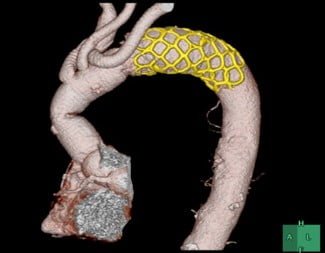

Aortic Stent Graft